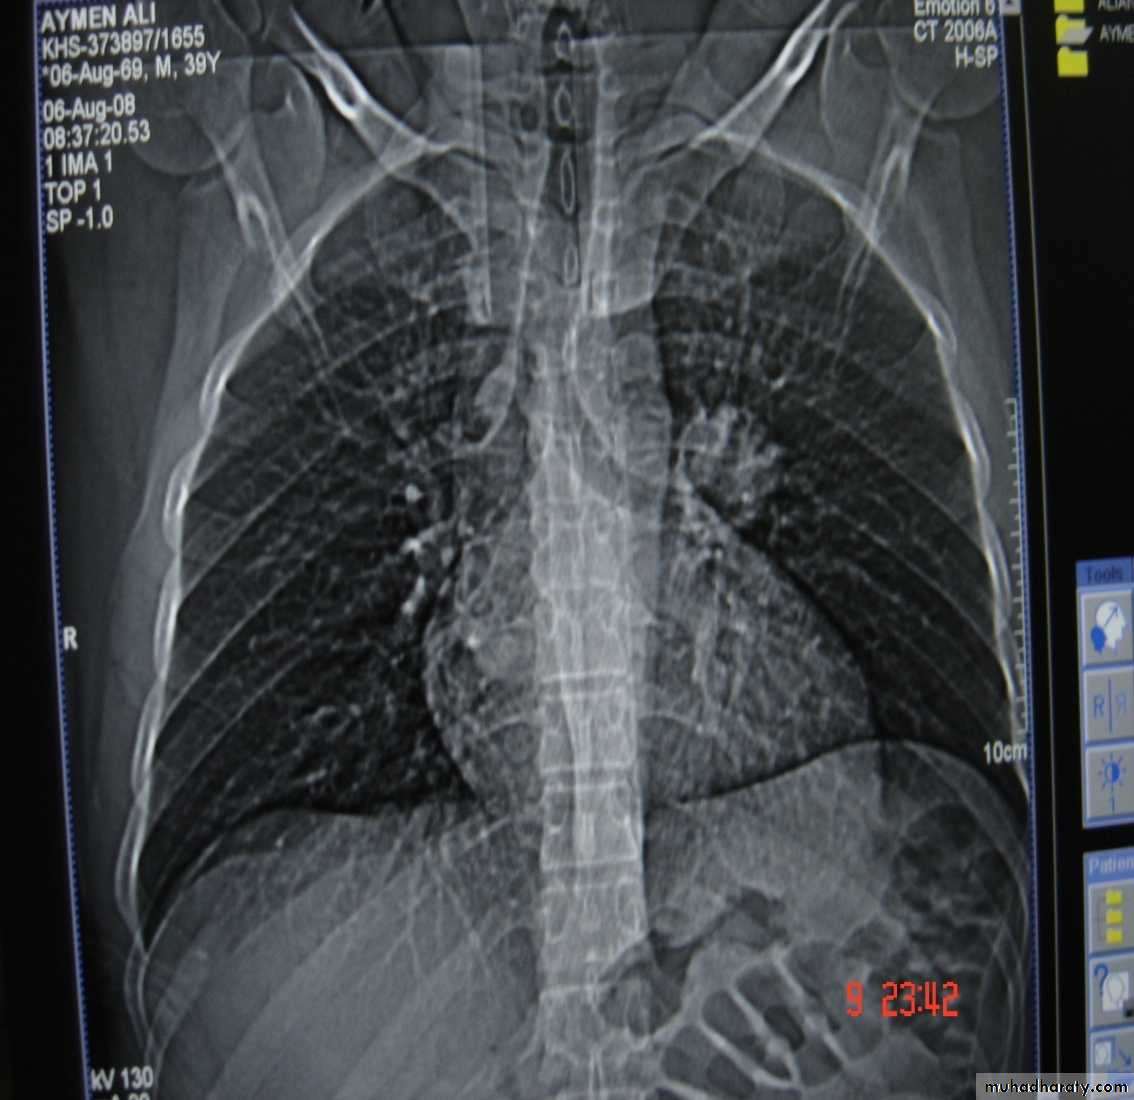

1-Chest X-Ray2-CT chest

3-MRI mediastinum